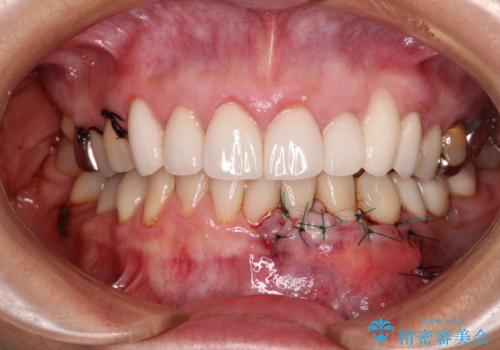

- 今まで知覚過敏の薬や歯磨き粉などを散々試しても全く改善されないとのことで来院された患者様です。

歯根面が露出しており、少し風をかけるだけでもしみてしまう状況でした。

セラミッククラウンによる治療も検討されていましたが、歯肉が非常に薄く、クラウンを装着しても将来的に歯肉退縮を起こす可能性が考えられたので、まずは歯肉移植による根面被覆を行うこととしました。

外科処置に恐怖心があるとのことで、移植手術を行う際には、静脈内鎮静法にてリラックスした状態で処置を受けていただきました(別途税別5万円)。